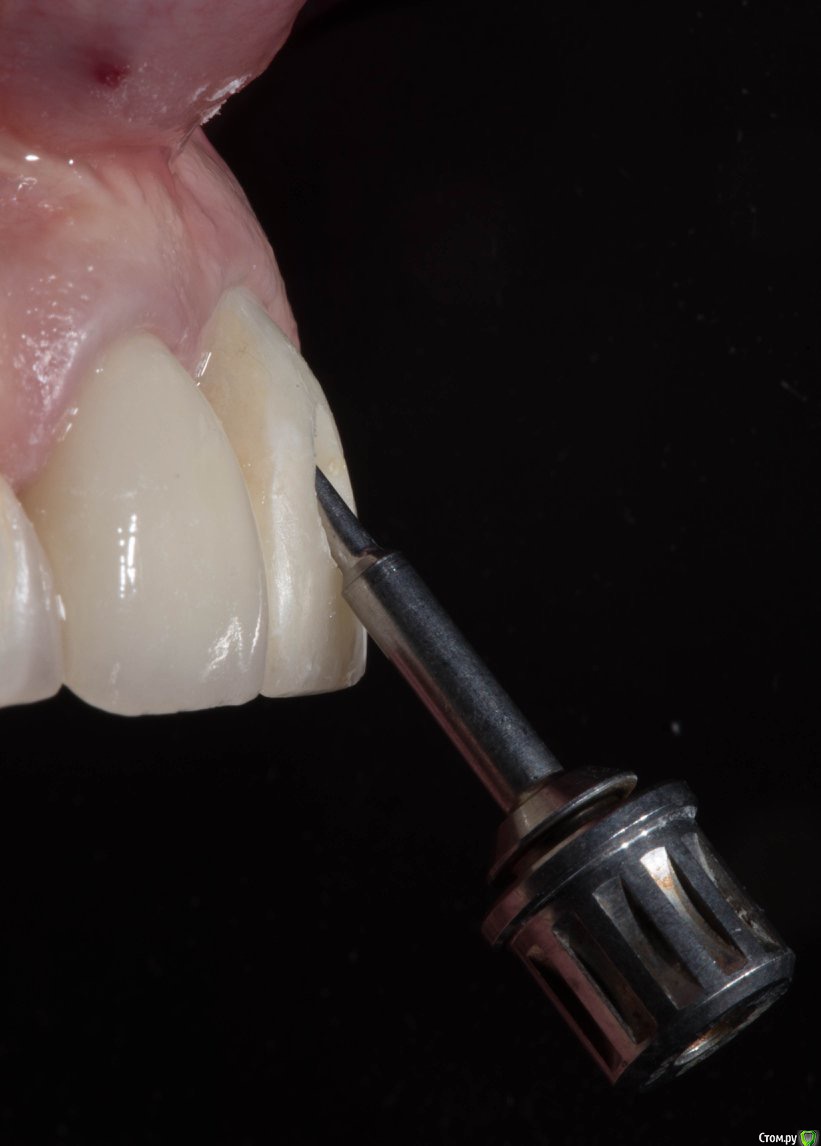

колесников Опубликовано 21 марта, 2018 Поделиться Опубликовано 21 марта, 2018 Можно,но не нужно. Размеры оптимальные. Немедленная нагрузка показана. Стремитесь к винтовой фиксации,длинный Имплант в этом случае будет сложно расположить. Удалять атравматично,лоскут не откидывать, Сст вестибулярно 1 Ссылка на комментарий

колесников Опубликовано 21 марта, 2018 Поделиться Опубликовано 21 марта, 2018 (изменено) Чтобы отвертка не уперлась в режущий край,ставить лучше более вертикально,Апекс в этом случае будет близко к вестибулярной компактной пластинке ,после нагрузки может быть окончатся резорбция. Мне кажется, 10 мм с заглублением, самое то. Изменено 21 марта, 2018 пользователем колесников 1 Ссылка на комментарий

Irouil Опубликовано 27 марта, 2018 Поделиться Опубликовано 27 марта, 2018 Мне кажется цемент во фронте это вызов для ортопеда. Доверяете ему? Выводите в куда удобно. Не доверяете? Только винт. Все мои ортопеды принципиально просят винтовую. Я обсуждал вопрос цемента с ними, кто-то готов учиться, кто-то нет, но заставлять людей обещать мне то, чего они не могут, я не могу. С точки зрения хирургии я рассматриваю имплантат как изделие, требующее обслуживания. Винтовая>цементная Ссылка на комментарий